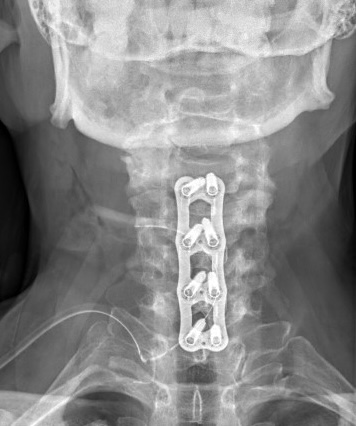

Krční páteř

Krční páteř operujeme nejčastěji z předního přístupu. Příčným řezem v tzv čárách štěpitelnosti kůže (vráskách) se dostaneme k postiženému segmentu páteře. Po odstranění meziobratlové ploténky a osteofytů, které utlačovaly nervové struktury nahradíme vyplníme meziobratlový prostor implantátem vyplněným kostním štěpem odebraným z lopaty kosti kyčelní a obratlová těla fixujeme speciální krční dlahou.

V případech víceetážového postižení krční páteře volíme operační přístup zadní.